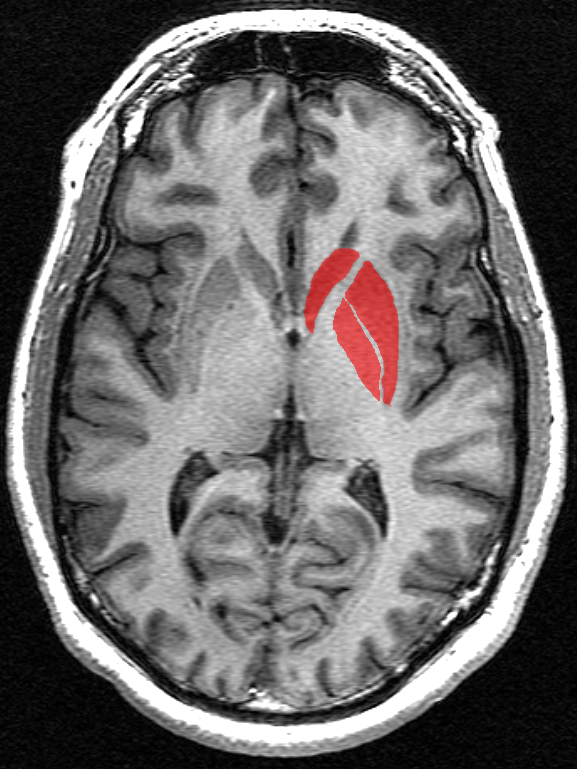

조가비핵은 전뇌에 위치한 구조로, 꼬리핵과 함께 배쪽선조체를 형성하며, 창백핵과 함께 렌즈핵을 구성한다. 기저핵의 가장 바깥쪽 부분으로, 운동 조절, 인지, 감정, 학습, 실행 기능 등 다양한 기능과 관련이 있다. 조가비핵은 운동 피질, 체감각 피질, 시상, 흑질 등과 연결되어 있으며, 신경전달물질인 도파민, GABA 등을 분비한다. 운동 계획, 학습, 운동 선택, 강화 학습, 범주 학습, 혐오 회로 등 다양한 기능에 관여하며, 파킨슨병, 알츠하이머병, 헌팅턴병, 뚜렛 증후군, 조현병 등 다양한 질병과 관련이 있다. 다른 동물에서도 유사한 구조와 기능을 보이며, 고차 인지 기능과 감각 운동 기능에 관여한다.

조가비핵은 전뇌에 있는 구조로, 꼬리핵과 함께 배쪽선조체를 형성한다. 많은 신경해부학자들은 이 둘을 내부 캡슐이라는 큰 섬유 다발에 의해 나뉜 단일 구조로 보기도 한다.[1] 조가비핵은 창백핵과 함께 렌즈핵을 구성하며, 기저핵의 가장 바깥쪽 부분이다. 기저핵은 대뇌 피질, 시상, 뇌간과 상호 연결된 뇌의 핵 그룹으로, 선조체, 흑질, 측좌핵, 시상하핵 등을 포함한다.

포유류에서 기저핵은 운동 조절, 인지, 감정, 학습, 실행 기능, 특정 영역 언어 지원 등 다양한 기능과 관련이 있다. 기저핵은 뇌 양쪽에 위치하며, 전두 및 미측 분할을 가진다. 조가비핵은 선조체의 일부로 전두 분할에 위치하며, 선조체를 통해 대뇌 피질로부터 입력을 받는다.

꼬리핵(위)과 조가비핵(오른쪽), 창백핵(왼쪽)이 포함되어 있음.">